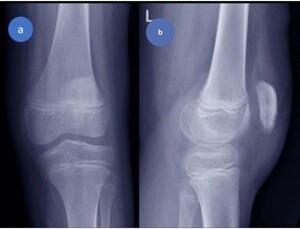

Investigations

At the emergency room, standard AP and lateral radiographs were performed, which revealed patella alta as well as a small osteochondral fragment at the inferior pole of the patella. (Figure 7). As a result of these radiographic findings, a patellar sleeve fracture was diagnosed.